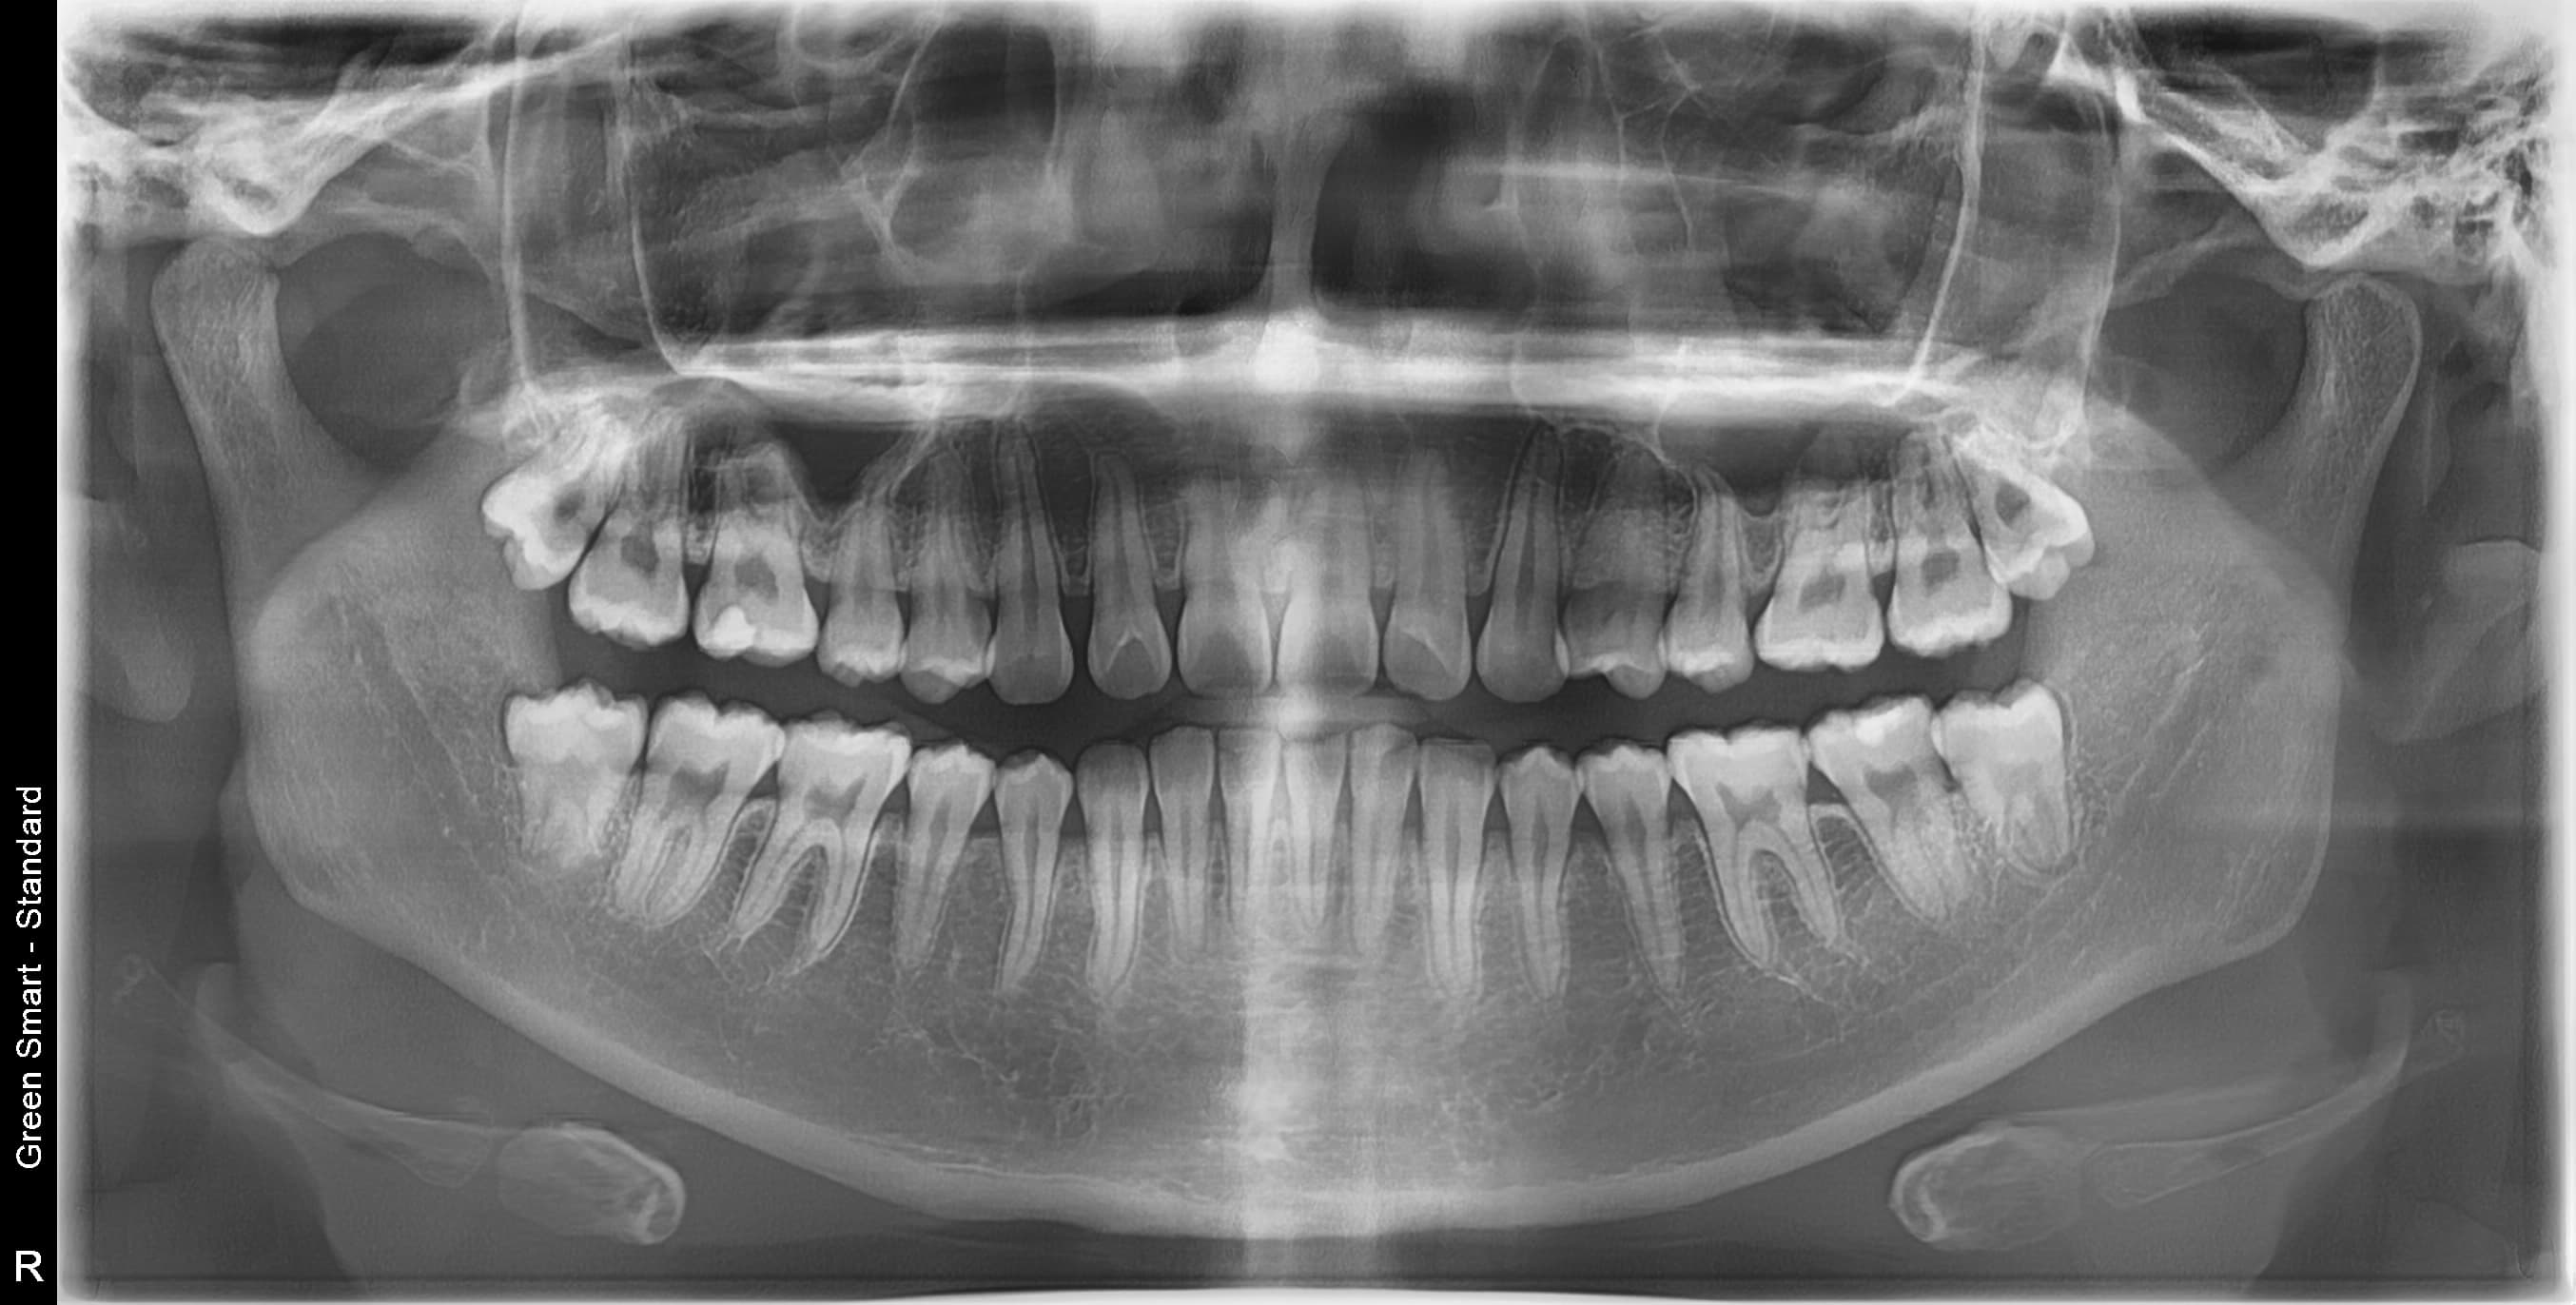

우리 병원 사랑니 발치의 특별함

2,700건 이상의 사랑니 발치 경험과 체계적인 시스템으로 차원이 다른 진료를 합니다

대학병원급 난이도 발치

일반 치과에서 "큰 병원 가보세요", "전문병원에서 빼세요" 이런 말 들어보셨나요?

복잡한 매복 사랑니 - 잇몸 속 깊이 묻혀있어도 OK

신경 근접 사랑니 - 신경 손상 걱정 없는 안전한 발치

수평 매복 사랑니 - 옆으로 누워있는 어려운 케이스도 가능

2,700건 이상의 발치 경험으로

대학병원 수준의 난이도도 안전하게 해결합니다